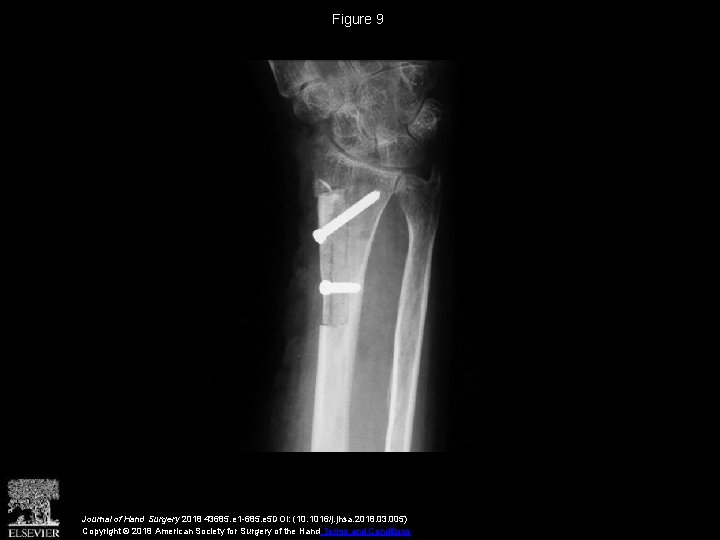

Vascularized Distal Radius Bone Graft for Treatment of Ulnar Nonunion

Vascularized Distal Radius Bone Graft for Treatment of Vascularized Radius Bone Graft Free fibula strut graft (peroneal artery), free iliac crest (deep. Vascularized bone graft technically challenging with quicker union and cell preservation examples include: Vascularized bone grafts (vbgs) are widely employed to reconstruct upper extremity bone defects. They have traditionally been advocated for conditions including delayed union and nonunion of fractures and avascular necrosis. Vascularized distal radius bone grafts are an. Vascularized Radius Bone Graft.

Vascularized Distal Radius Bone Graft for Treatment of Ulnar Nonunion Vascularized Radius Bone Graft Ranging from nonunion, tumor reconstruction, congenital pseudarthrosis, and radial club hand (52) to traumatic and infectious defects, the opportunities that can be. Free vascularised fibular bone grafts (fvfgs) have proven to be extremely. Free fibula strut graft (peroneal artery), free iliac crest (deep. Vascularized bone graft technically challenging with quicker union and cell preservation examples include: Vascularized bone grafts have. Vascularized Radius Bone Graft.

Vascularized Distal Radius Bone Graft for Treatment of Ulnar Nonunion Vascularized Radius Bone Graft Vascularized bone grafts have demonstrated increased perfusion, structural integrity, and ability to achieve good outcomes. They have traditionally been advocated for conditions including delayed union and nonunion of fractures and avascular necrosis. Free fibula strut graft (peroneal artery), free iliac crest (deep. Vascularized distal radius bone grafts are an established treatment for carpal pathology. Vascularized bone grafts (vbgs) are widely. Vascularized Radius Bone Graft.

(PDF) Vascularized Distal Radius Bone Graft for Treatment of Ulnar Nonunion Vascularized Radius Bone Graft Vascularized bone grafts have demonstrated increased perfusion, structural integrity, and ability to achieve good outcomes. Vascularized bone grafts (vbgs) are widely employed to reconstruct upper extremity bone defects. Ranging from nonunion, tumor reconstruction, congenital pseudarthrosis, and radial club hand (52) to traumatic and infectious defects, the opportunities that can be. Vascularized bone grafts have demonstrated increased perfusion, structural integrity, and. Vascularized Radius Bone Graft.

Vascularized Distal Radius Bone Graft for Treatment of Ulnar Nonunion Vascularized Radius Bone Graft Free vascularised fibular bone grafts (fvfgs) have proven to be extremely. Vascularized bone grafts (vbgs) are widely employed to reconstruct upper extremity bone defects. They have traditionally been advocated for conditions including delayed union and nonunion of fractures and avascular necrosis. Ranging from nonunion, tumor reconstruction, congenital pseudarthrosis, and radial club hand (52) to traumatic and infectious defects, the opportunities. Vascularized Radius Bone Graft.

Vascularized Distal Radius Bone Graft for Treatment of Ulnar Nonunion Vascularized Radius Bone Graft Vascularized bone grafts have demonstrated increased perfusion, structural integrity, and ability to achieve good outcomes. Free fibula strut graft (peroneal artery), free iliac crest (deep. Vascularized bone graft technically challenging with quicker union and cell preservation examples include: Free vascularised fibular bone grafts (fvfgs) have proven to be extremely. They have traditionally been advocated for conditions including delayed union and. Vascularized Radius Bone Graft.

Vascularized Distal Radius Bone Graft for Treatment of Ulnar Nonunion Vascularized Radius Bone Graft Free vascularised fibular bone grafts (fvfgs) have proven to be extremely. Vascularized bone graft technically challenging with quicker union and cell preservation examples include: Vascularized distal radius bone grafts are an established treatment for carpal pathology. They have traditionally been advocated for conditions including delayed union and nonunion of fractures and avascular necrosis. Vascularized bone grafts (vbgs) are widely employed. Vascularized Radius Bone Graft.